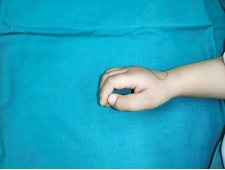

在孩子的成长过程中,家长们总是细心观察每一个成长的细节,希望孩子能够健康快乐地成长。然而,有些问题可能并不是一眼就能发现的。三岁的乐乐(化名)就是一个典型的例子。乐乐的双手拇指偏斜畸形,这个问题在他很小的时候就已经存在,但由于家人对这一症状缺乏足够的认识,导致问题逐渐加重。

乐乐的家人最初发现他的手指有些不寻常,但他们抱着一线希望,认为随着孩子的长大,手指会逐渐变直。然而,两年多的时间过去了,乐乐的拇指偏斜畸形不仅没有改善,反而逐渐加重。这时,家人才意识到问题的严重性,决定带乐乐去医院进行检查。

乐乐的拇指偏斜程度虽然不是很严重,但这并没有引起家人的重视。他们尝试了保守治疗,但效果并不理想。面对这种情况,唯一能够解决问题的方法就是手术。滕医生根据乐乐的具体情况,设计了一套手术方案。手术中,医生将拇指中节的“Delta”骨去除,进行了韧带紧缩修复,并使用克氏针固定,以改善拇指的外形。

手术后,乐乐的手指外观得到了明显的改善。然而,滕医生也提醒广大家长,导致拇指偏斜的原因有很多,手术方式也会因此而有所不同。如果家长发现孩子的手指有任何异常,应尽快到专业的小儿骨科就诊,以便得到准确的诊断和及时的治疗。